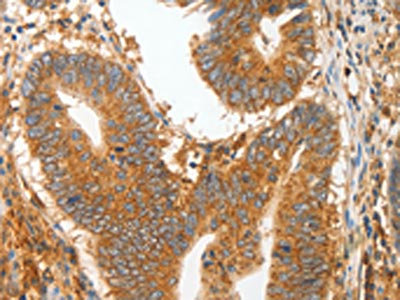

The image on the left is immunohistochemistry of paraffin-embedded Human colon cancer tissue using CSB-PA789328(MMP28 Antibody) at dilution 1/20, on the right is treated with fusion protein. (Original magnification: ×200)